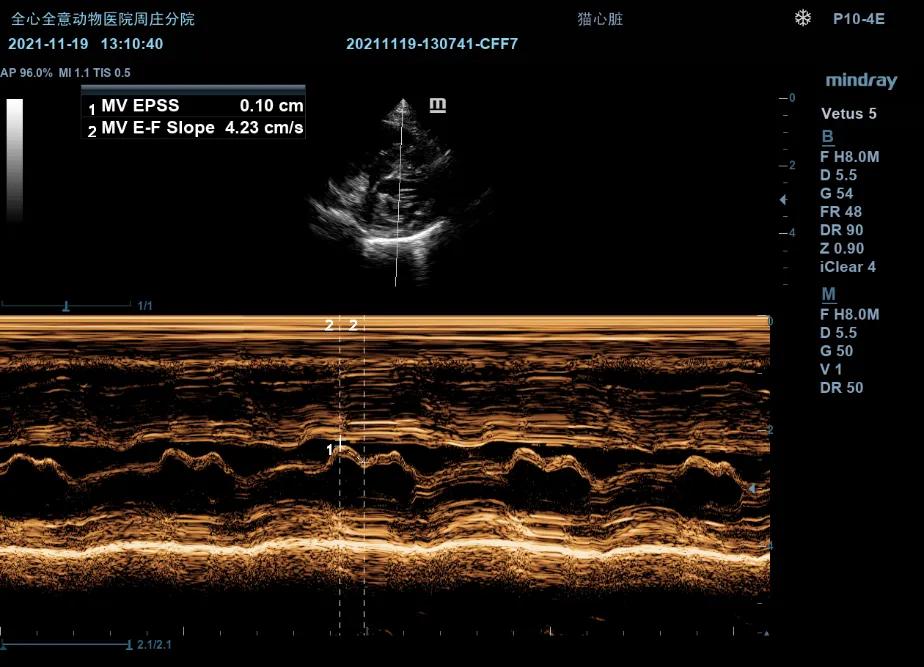

右侧短轴二尖瓣观(M型):

EPSS:0.11cm

E-F Slope:4.23cm/s

C点至D点二尖瓣运动轨迹异常。